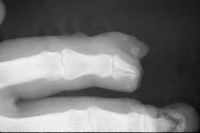

| Case

4. A dog bit off this young man's index fingertip. Although the PA Xray looks as though the bone was kept, additional views show an amputation through the tuft. |